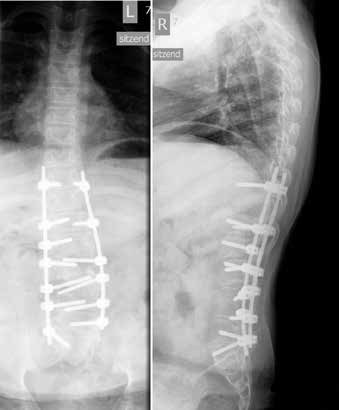

Im Alter von zwei Jahren kam es zu einem Tethered Cord. Die Wirbelsäule wurde im Alter von vier Jahren aufgrund einer thorakalen Gibbusdeformität nach Kyphektomie und Revision nach Stabbruch bis auf Höhe TH10 versteift (Abb. 2). Des Weiteren liegt eine neurogene Blasen- und Darmentleerungsstörung vor. Aufgrund von Shunt-Fehlfunktionen kam es immer wieder zu starken Kopfschmerzen und Gleichgewichtsstörungen. Vertikalisierende Orthesenversorgungen konnten in diesem Zeitraum kaum genutzt werden. Nach zwei vollständigen Shuntrevisionen konnten die Symptome behoben werden, sodass eine Neuversorgung mit einer Orthese wieder möglich war.